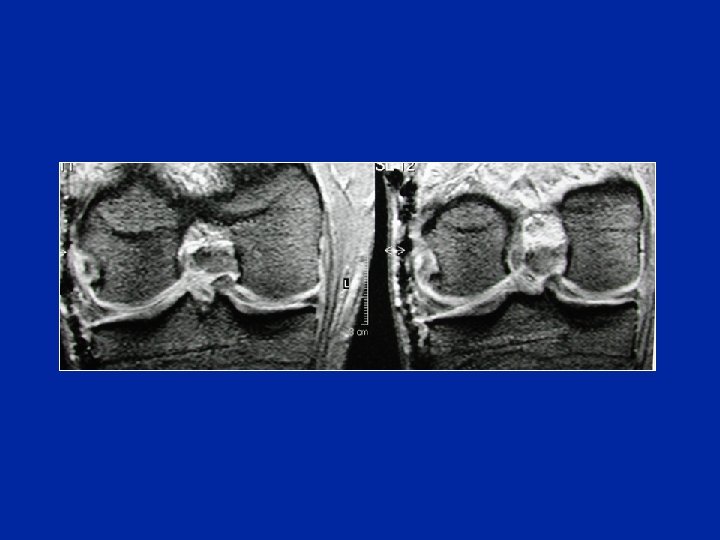

Aspecto de doble LCP Asa de balde luxada Asa de balde del Menisco Interno

Asa de balde del Menisco Interno